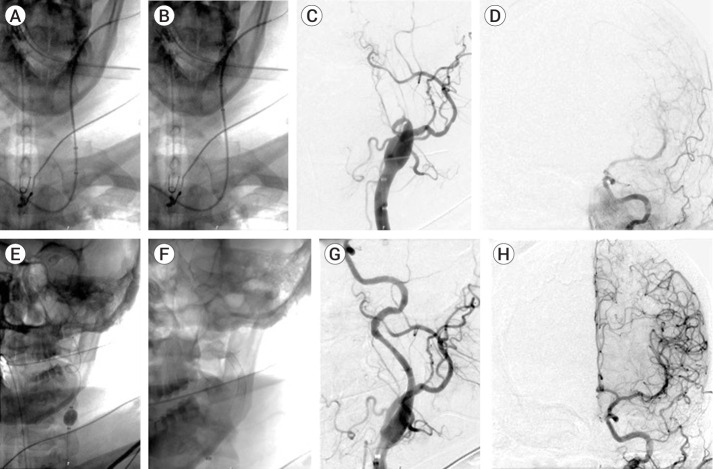

Intro: There is a growing preference among neurointerventionalists for transradial access (TRA) over transfemoral access (TFA) due to improved patient satisfaction, recovery time and reduced access site complication, but using balloon guide catheters (BGCs) in the radial artery remains a challenge. We report our experience in successfully using the 0.087" inner diameter Walrus BGC without a sheath via the radial artery for non-emergent neurointerventions.

Objective: Describe the technique for safely accessing the radial artery using the sheathless Walrus balloon guide catheter.

Methods: A retrospective chart review of thirteen consecutive patients who underwent intervention with radial artery access with a sheathless Walrus BGC was performed.

Results: All twelve procedures were performed successfully with no instances of conversion from TRA to TFA. There were no significant procedural or access site complications. The mean radial diameter was 2.51 mm.

Conclusions: The Walrus 0.087" ID BGC is an effective tool that can safely be used via the radial artery using a sheathless approach, which helps to maximize the size of the catheter that can be used. This is the first instance of our knowledge of this technique being utilized for neurointerventions and therefore could be used to expand the indications for TRA for a wider range of procedures.